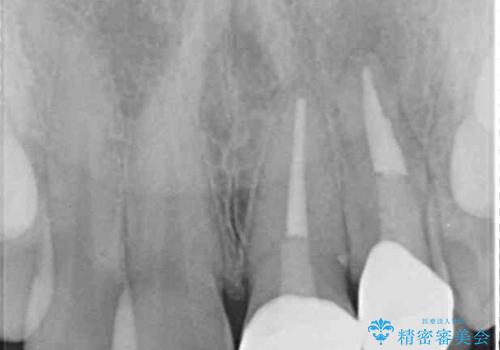

既にクラウンが装着されていた歯は歯根の先端に病変が認められたため、根管治療を行うこととしました。